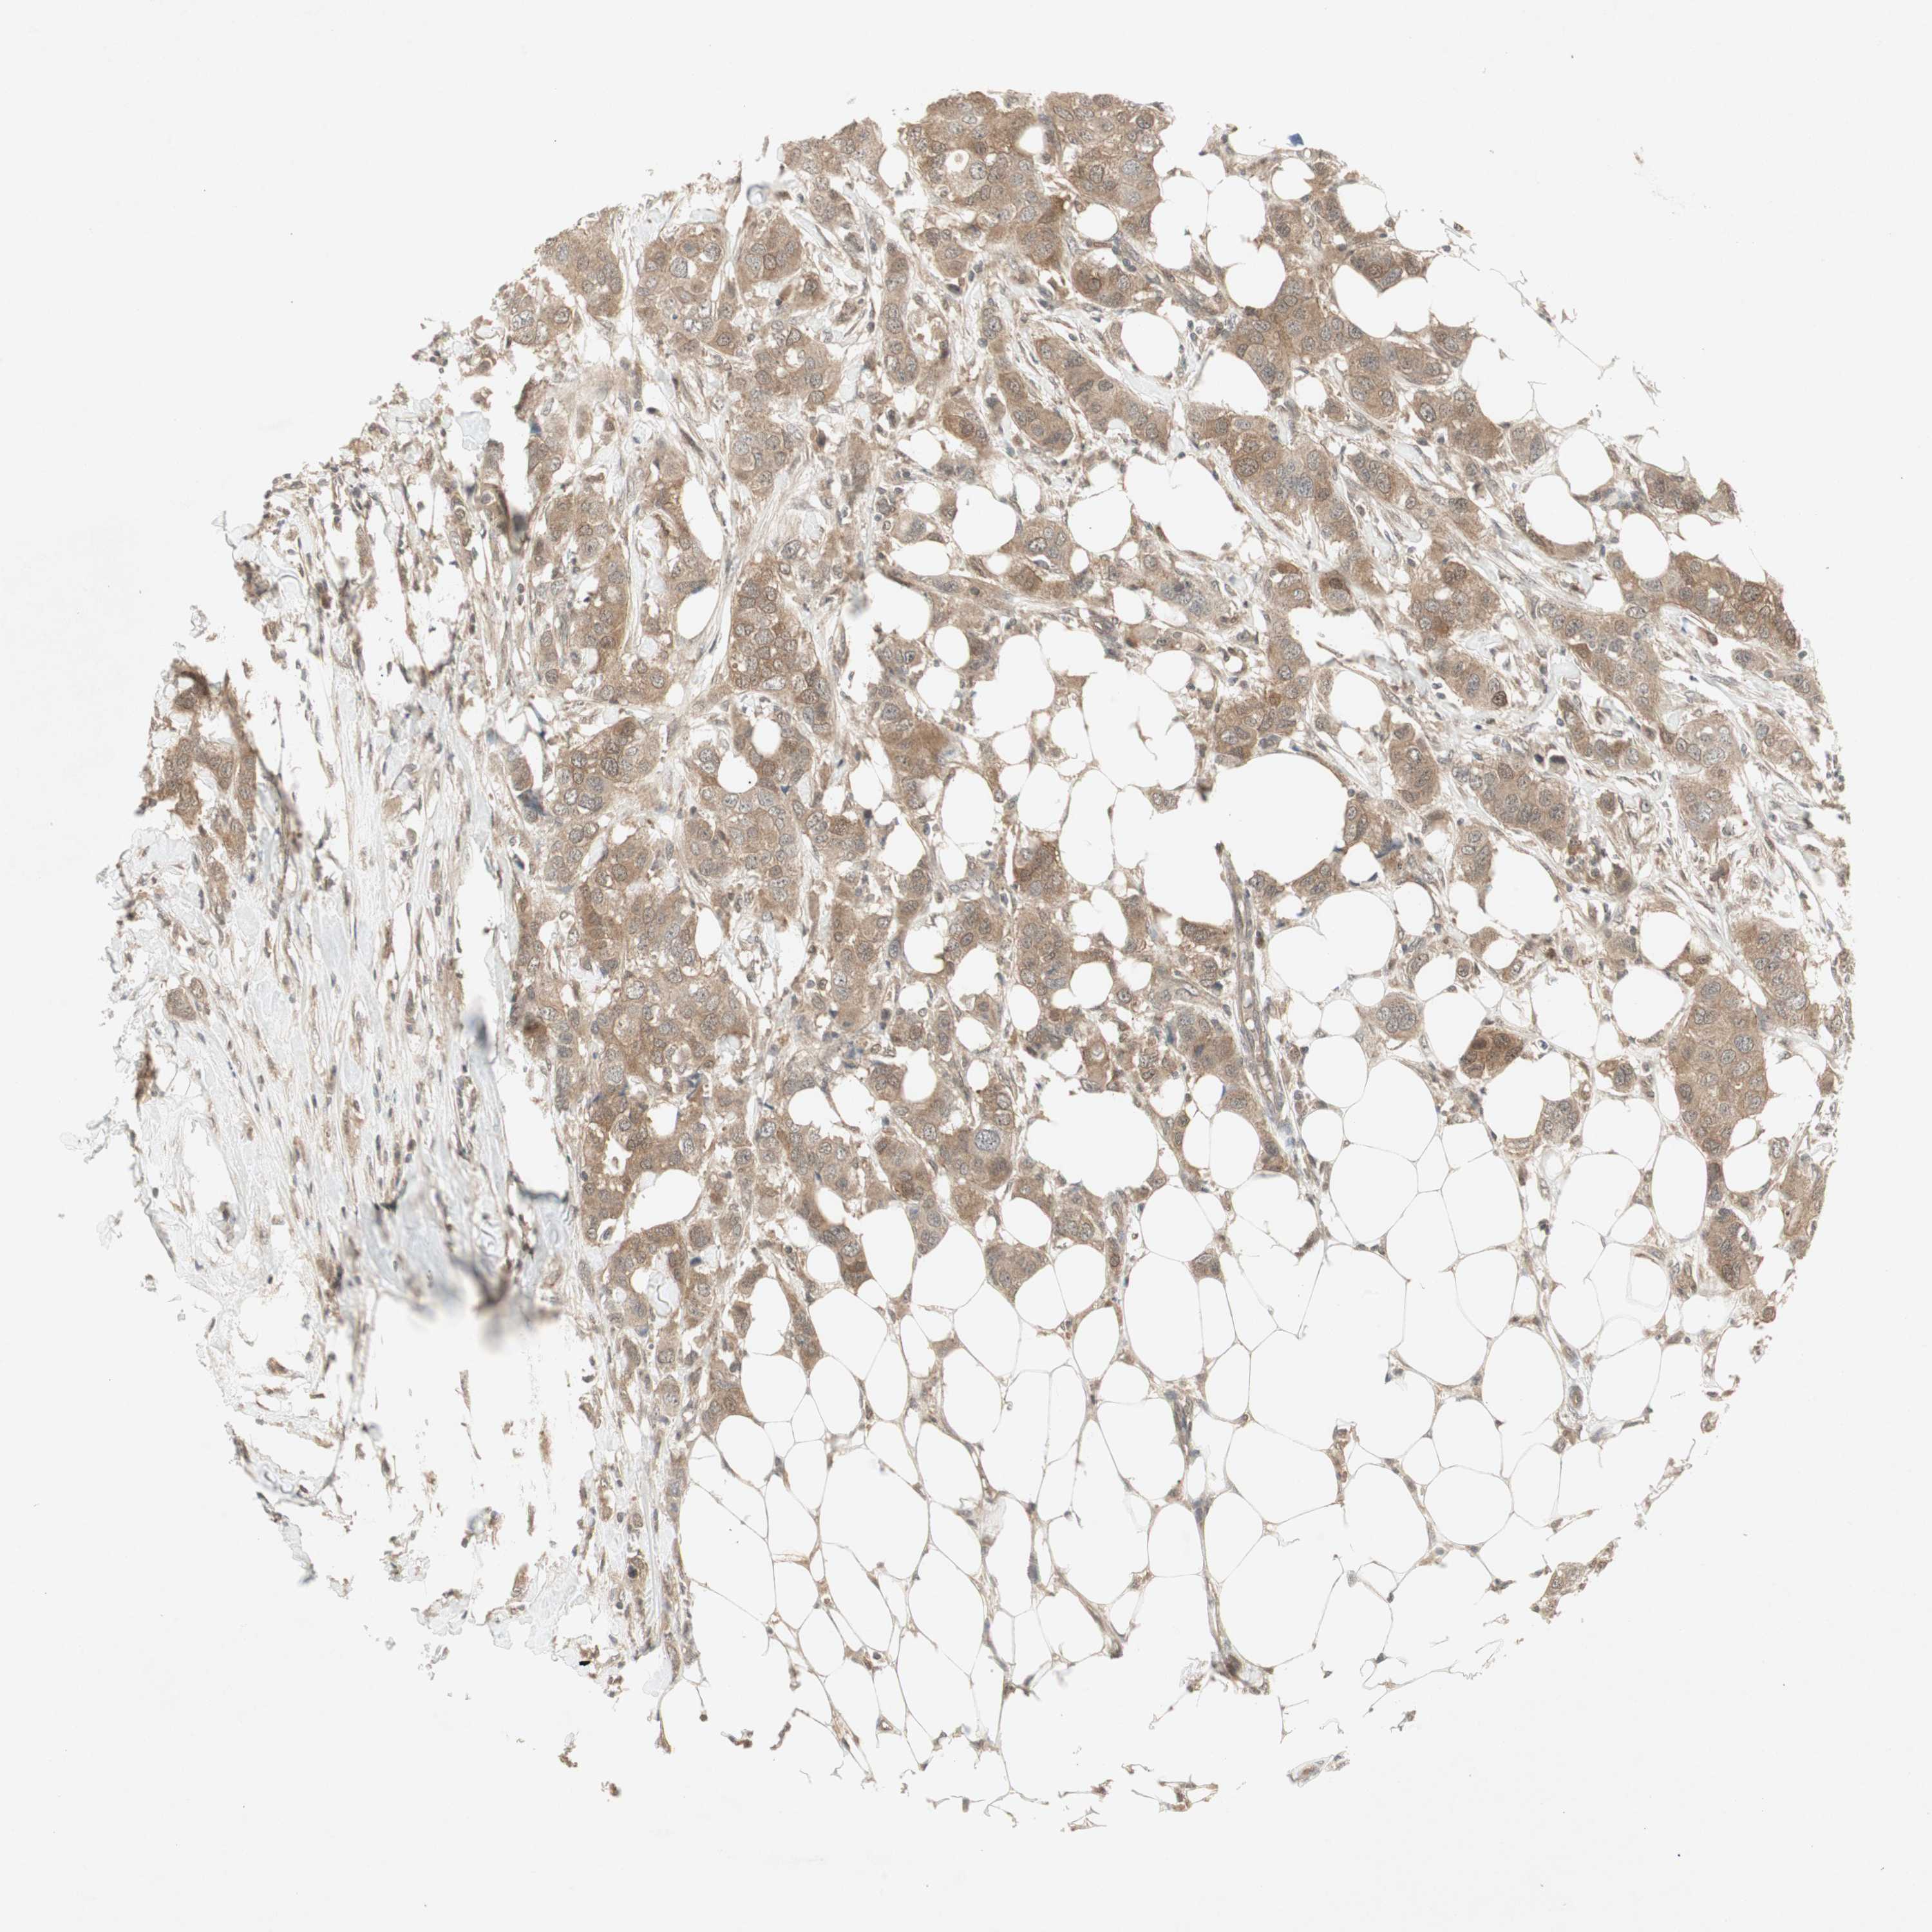

BRCA TCGA BRCA VALIDATION PROTEIN EXPRESSION

ANTIBODIES

AND

VALIDATION